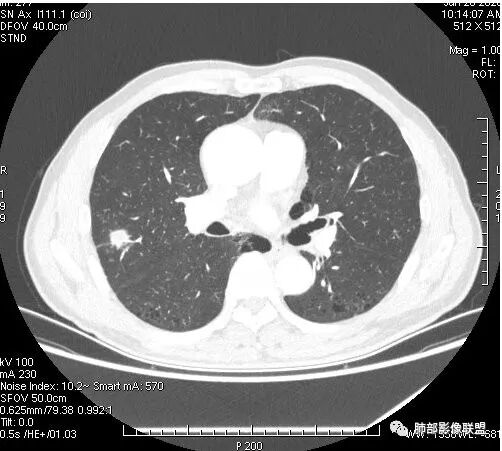

影像学改变:

1.右肺上叶后段类圆形结节影,密度不均,有坏死空洞,坏死比较彻底,内外壁都较清楚。

2.病灶有浅切迹,没有深分叶,毛刺大多细长且柔软。

3.可见棘状突起及胸膜牵拉,但未见胸膜凹陷。

什么意思?结节影有牵拉的动作,但似乎“出工不出力”,收缩力羸弱!

4.病灶轻到中度强化。病灶内血管走行较完好,病灶旁血管局部显示粗大。

5.支气管关系不确定。

6.灶周见小结节影(卫星灶),边界不甚清晰。